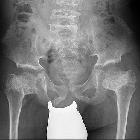

X-ray of 7

yrs old girl with spondylometaphyseal dysplasia type Kozlowski showing femoral metaphyseal deformity and moderate platyspondylia

Spondylometaphysärer

Dysplasie Typ Koslowski: Röntgenbild des Beckens mit Darstellung der deformierten Femurmetaphysen. Platyspondylie der mit erfassten unteren Wirbel.